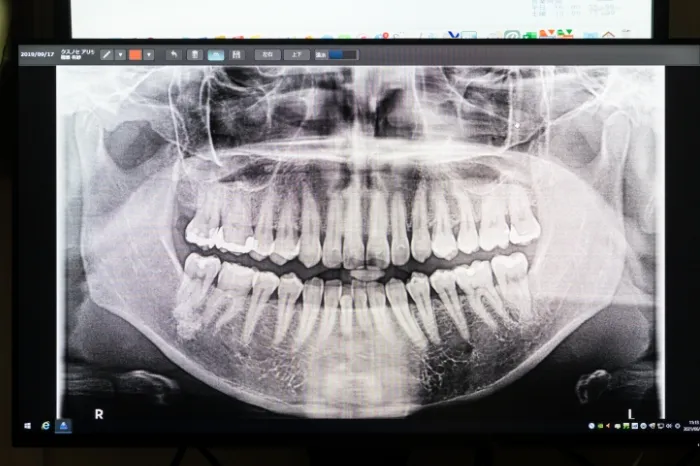

- 歯科用CT

- デジタルレントゲン